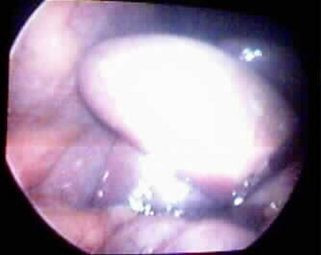

Post Image

Vesícula atrófica